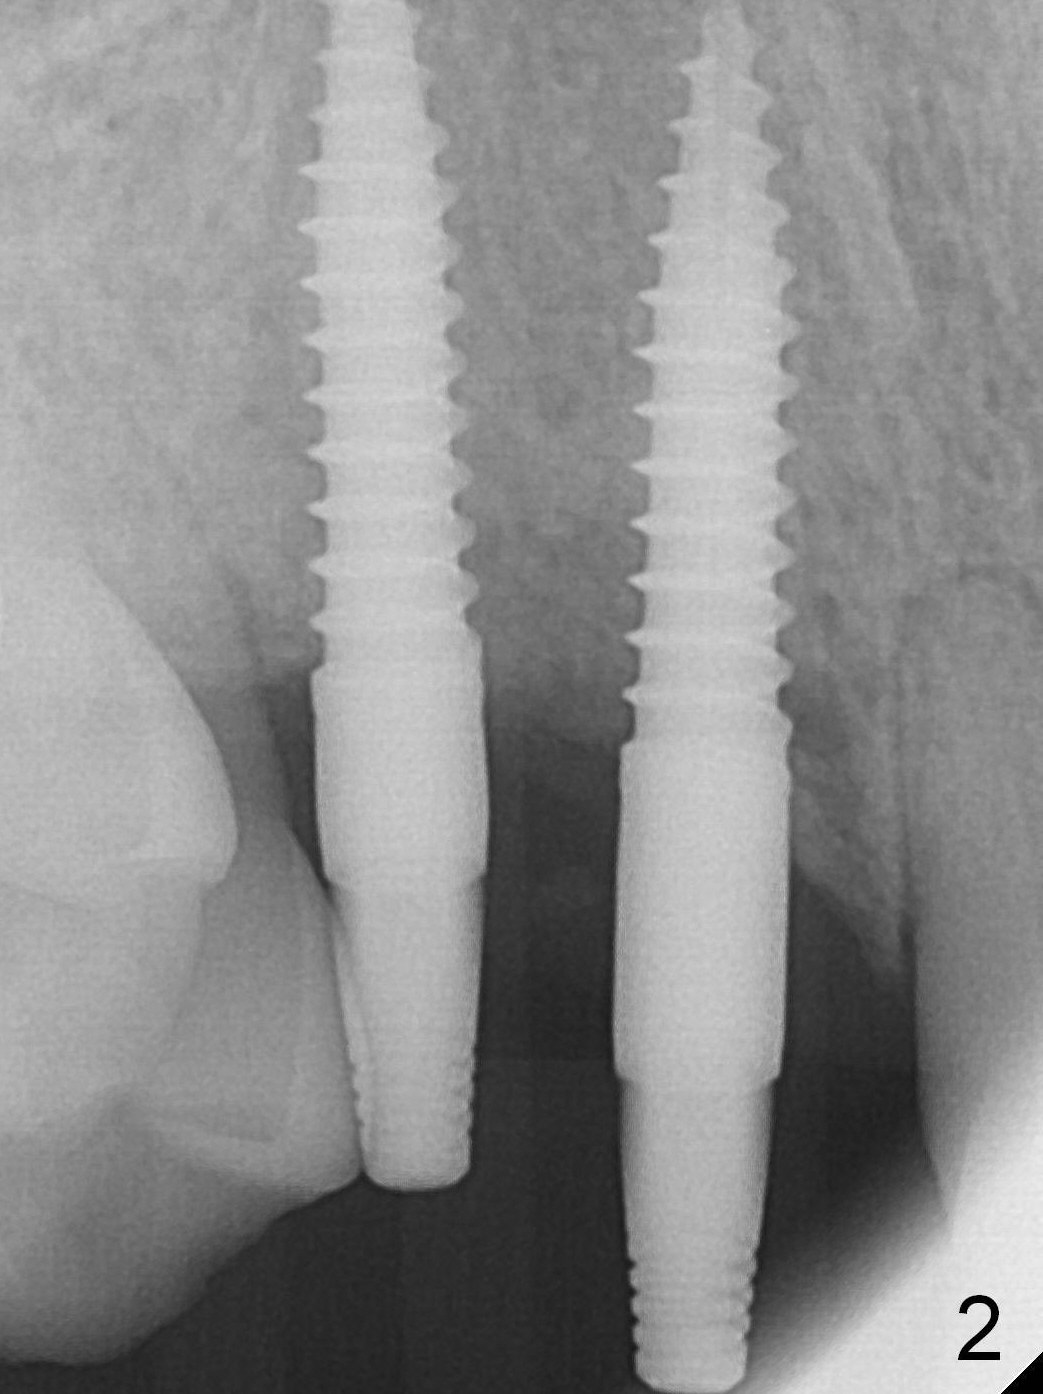

The ridge at the sites of #6 and 7 looks wide, but the bone is narrow (~ 4 mm) when the flaps are raised.  Two of 3 mm 1-piece implants (3x16(2) and 3x14(4) mm) are placed (Fig.1,2).  The other advantage of use of 1-piece implants is the narrow mesiodistal space.  In fact the gingiva is wide and thick (4 mm).  It is ideal to place implants with 4 mm cuff; unfortunately there is no 3x16(4) mm implant available at the site of #6.  After adjustment of the abutment at #7, a splinted provisional is fabricated.